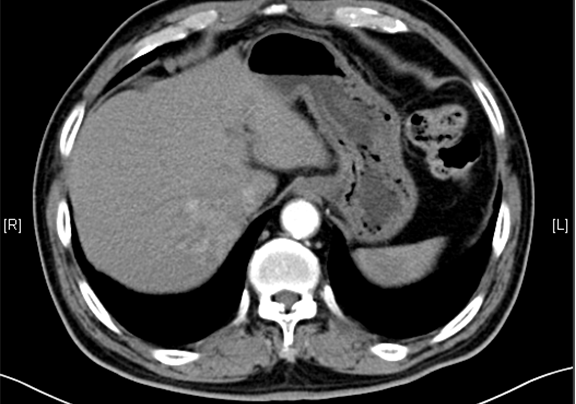

随访情况:

随访8天,复查CT肝部分切除术后所见,肝右后叶斑片状低密度影。

肝切除术后肝脏体积1周:1周:□ml 1月:□ml 3月:□ml 6月:□ml 1年:□ml